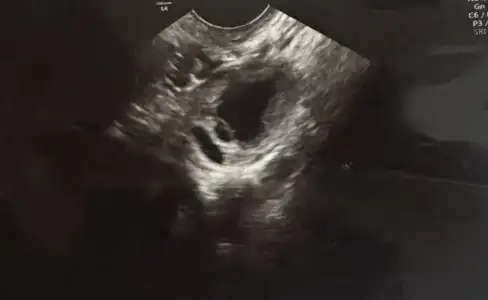

Merhabalar, sizler gibi 1 senedir çocuk düşünüyorum.Bu ay 2. Klomen kullanışım.Sat 15 mayıstı.10.günü 22 mmlik yumurtam için çatlatma iğnesi vuruldum.dün doktor kontrolüm vardı, çatlatmadan 5 gün sonra.Doktor ultrasondan yumurtamın çatladığını söyledi.biz çatlatma öncesi, çatlatma günü ve sonrasındaki 3 günü değerlendirmiştik.Son 2 gündür ilişki olmadı.Bu sabah da akıntım başladı.Merak ettiğim ultrason görüntüsü o şekilde kaç gün kalır?Yanlış günlerde mi ilişkiye girdik acaba yumurtam çatlamamıştı ve boşa gitti? Çok korkuyorum ve çok merak ediyorum bilgisi olan var mı?